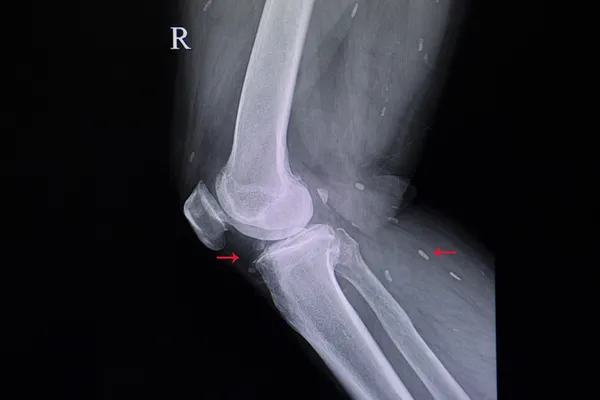

"Diz kireçlenmesi her hastalıkta olduğu gibi muayene ile teşhis koyulmaktadır. Problemin ne olduğu, kireçlenmenin ne evrede olduğu ve tanının doğru olduğu belirlenerek, röntgen, MR çok nadiren tomografi, bazen de bacak uzunluk filmleri ile destekleyerek tedavi tanımlanmaktadır. Diz kireçlenmesinin birçok tedavi yöntemleri bulunmaktadır. Bu yöntemleri genellikle hastanın kireçlenmesinin evresi, hastanın ek hastalıkları, hastanın uzman hekimden beklentilerine göre, bazı tedaviler uygulanmaktadır. Bu tedaviler basit istirahat, buz uygulama, ağrı kesici kullanımı, diz içi siteroid kıkırdak iğneleri, kapalı diz ameliyatlarıyla içeriye girip dizdeki, kıkırdağa canlandırıcı bazı işlemler yapmak, kıkırdak ameliyatlarıyla, kıkırdak nakli yapmak, kireçlenme olduğu için menisküslerde hasar görmekte, menisküsü rahatlatmak için, temizlik ameliyatları yapmak veya diz protezi gibi tüm diz eklemi çıkartılıp yerine metalden yukarıya ve aşağıya doğru eklemini taklit eden implantlar koyup araya da erimeyen plastik parça koyarak birçok tedavi uygulanmaktadır. Diz kireçlenmesi olduktan sonra geriye dönen bir hastalık değildir. Tamir edilemediği için, farklı tedaviler uygulanmaktadır. Diz kireçlenmesi olacağını, diz kireçlenmesi yaşayacağını, özellikle kırklı yaşlarda bazı problemleri olan hastalarda ortopedik cerrahlar anlayabilmektedir. Mesela, kıkırdak ilerde diz kireçlenmesi dönmektedir. Menisküs hasarı ilerde diz kireçlenmesine dönmekte, dizi zorlayıcı işlerde çalışan insanlar, ilerde diz kireçlenmesi yaşayabilmektedirler. Fazla kilolu insanlar ilerde diz kireçlenmesi yaşayabilmektedir. Bu hastalar henüz kireçlenme yakalanmadıysalar bazı basit önerilerle bilgilendirildiklerinde ve hastalar bu önerilere uyduklarında ileride yaşanacak diz kireçlenmesi sorunu engellenmiş olacaktır."